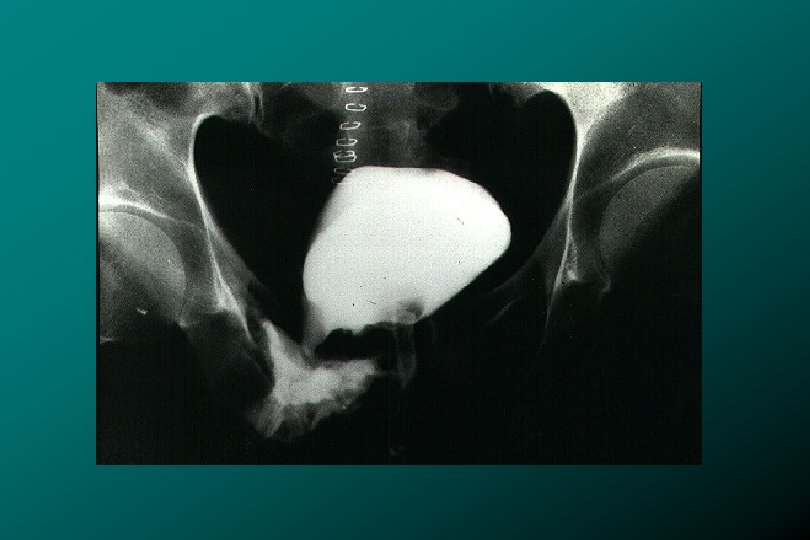

TRAUMA DE URETRA POSTERIOR REPARO INMEDIATO • • Hemodinámicamente estable. Inminente exploración pélvica. Desplazamiento

TRAUMA DE URETRA POSTERIOR REPARO INMEDIATO • • Hemodinámicamente estable. Inminente exploración pélvica. Desplazamiento severo de próstata y vejiga. Laceración importante de cuello vesical. * Zegarra L. : Traumatismos Urológicos. En: Barboza ed. Principios y Terapéutica Quirúrgica. Lima: De Arteta Imp. 1999: 576 -590.